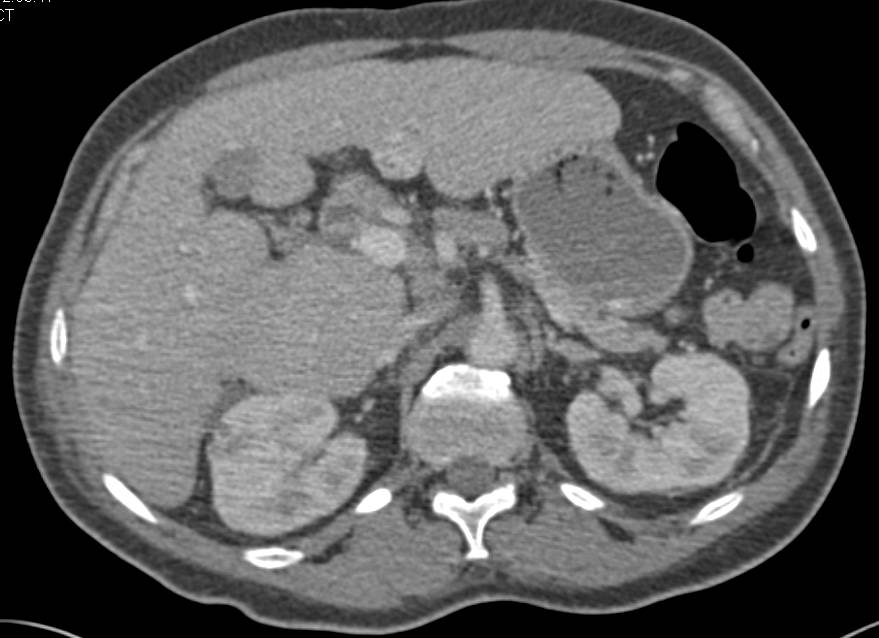

Recurrent Renal Cell Carcinoma Metastatic to the Liver with Vascular Metastases